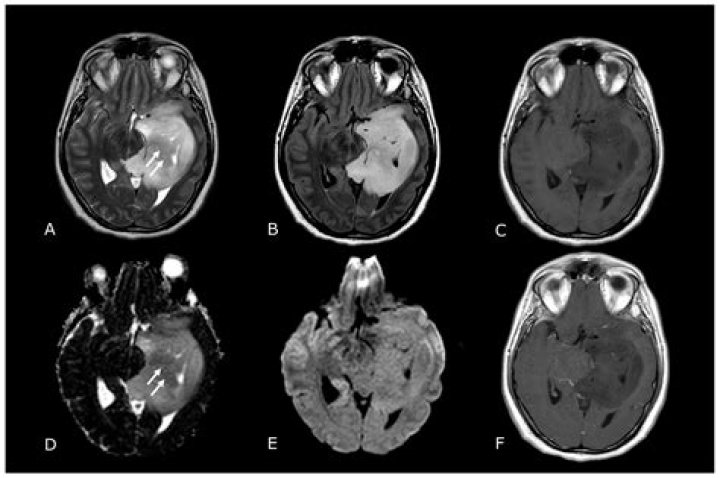

Malignant and Benign Tumors on MRI Scan

How do tumors look on MRI?

MRI creates pictures of soft tissue parts of the body that are sometimes hard to see using other imaging tests. MRI is very good at finding and pinpointing some cancers. An MRI with contrast dye is the best way to see brain and spinal cord tumors. Using MRI, doctors can sometimes tell if a tumor is or isn't cancer.